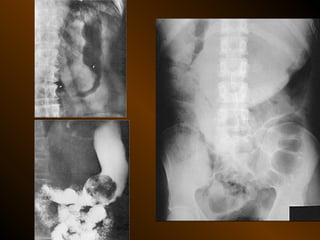

CĂNG GIÃN ỐNG TIÊU HÓA

TỤ KHÍ NGOÀIPHÚC MẠC • Nguyên nhân : – Thủng tạng rỗng – Áp xe tạo khí • X quang quy ước • Siêu âm • XQCLĐT